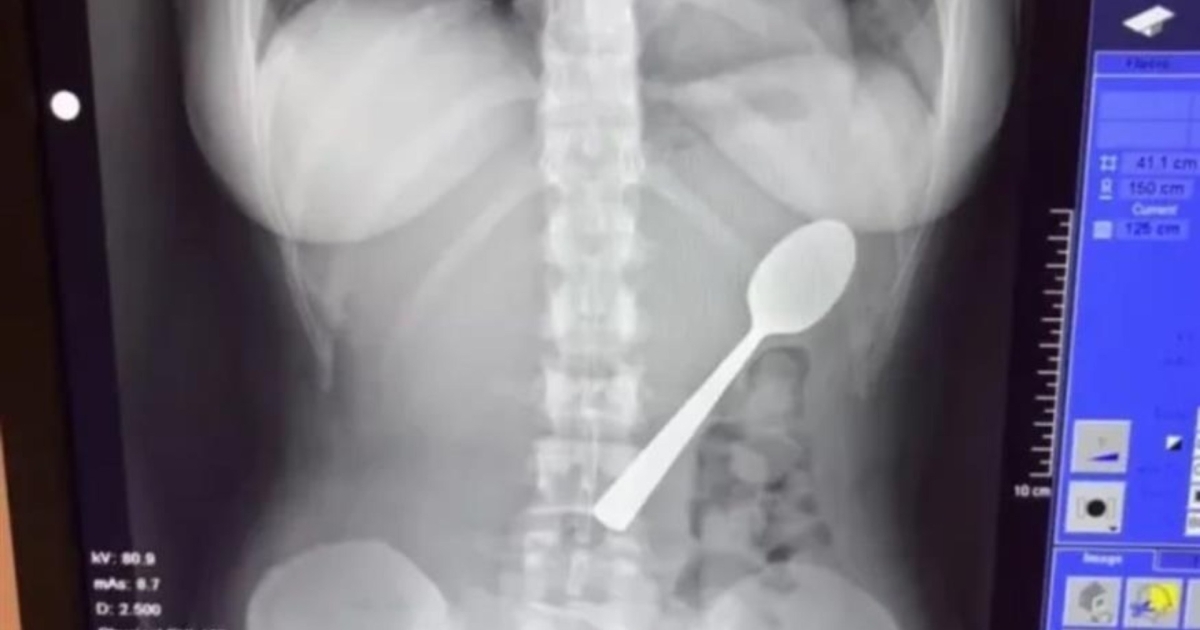

Βέλγιο: 28χρονη κατάπιε κουτάλι 17 εκατοστών όταν πήδηξε πάνω της ο σκύλος της

Όταν ο σύντροφός της επέστρεψε στο σπίτι, εκείνη δεν του αποκάλυψε τι είχε συμβεί, κυρίως από αμηχανία. Αρχικά δεν ένιωθε έντονη ενόχληση: «Το περίεργο είναι ότι δεν ένιωθα άσχημα. Καμία δυσφορία. Όμως μετά το δείπνο κατάλαβα ότι δεν μπορούσα να το αγνοήσω», εξήγησε. Απευθύνθηκε τελικά σε γιατρούς, οι οποίοι διαπίστωσαν ότι το κουτάλι ήταν πολύ μεγάλο για να αποβληθεί φυσιολογικά και έπρεπε να προγραμματιστεί γαστροσκόπηση.

Δύο ημέρες αργότερα, οι γιατροί αφαίρεσαν το κουτάλι με ενδοσκοπική διαδικασία και αναισθησία. Χρειάστηκε να το περιστρέψουν μέσα στο στομάχι, κάτι που προκάλεσε μικρή γαστρική αιμορραγία, αλλά η επέμβαση στέφθηκε με επιτυχία.